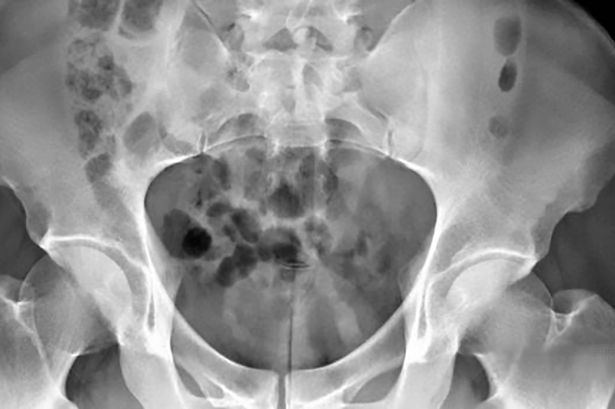

gif_animation 台湾にて、「尿道オナニー」にハマった男性(30歳)が長さ20cmのアダルトグッズを尿道に挿入、抜けなくなり病院へ運ばれたというニュース。アダルトグッズは膀胱にまで達していたそう…。(※ TOP画はイメージ)[5]images